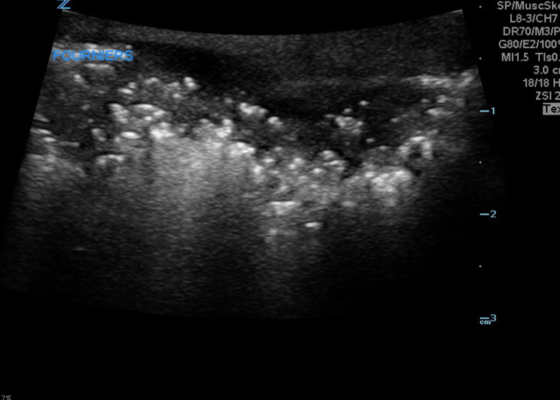

DOI: https://doi.org/10.21980/J8CP99Point of care ultrasound (POCUS) utilizing a high-frequency linear probe revealed heterogeneous debris with subcutaneous air within the scrotal wall extending into the perineum consistent with necrotizing fasciitis of the perineum or Fournier’s gangrene (FG). The video shows multiple foci of gas that appear as echogenic dots with “dirty shadows” posteriorly from reverberation artifact arising from gas within the soft tissue.